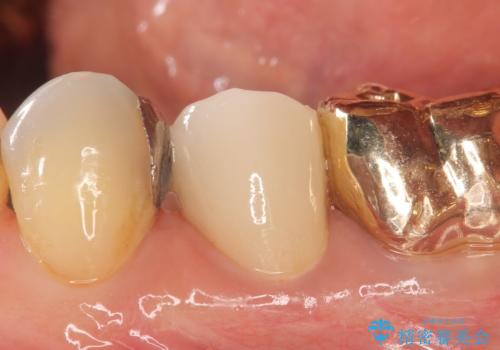

- 左下5番目の歯を根管治療からやり直したいといらっしゃった方の症例です。

再根管治療終了後、オールセラミッククラウンによる補綴を行いました。

今回用いたオールセラミッククラウンはジルコニアフレームという白い素材の上にセラミックを盛っているため、審美性が非常に高いのが特徴です。

また、ジルコニアは人工ダイヤモンドの材料にも使われているほど高い強度を持っており、そのためオールセラミッククラウンは審美性だけでなく、奥歯やブリッジの補綴も可能とするクラウンです。